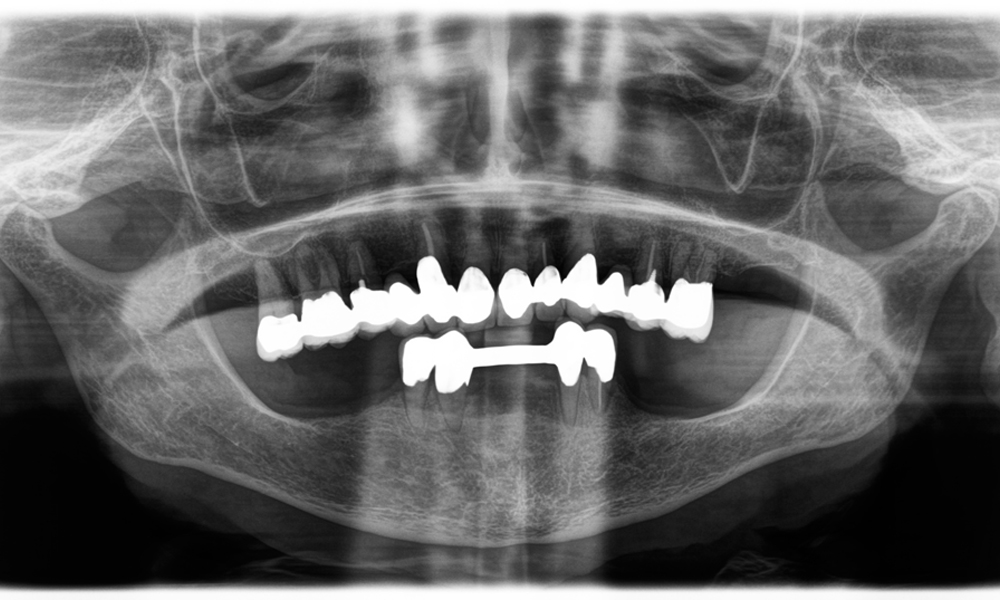

Otro ejemplo del rendimiento clínico de Power Edition fue la sustitución de una corona de zirconio dañada en una paciente de 63 años. El daño se produjo debido a la rotura de una parte del revestimiento de la corona de zirconio de 20 años de antigüedad en el diente 6. A pesar de encontrarse en la zona posterior, a la paciente le molestaba y deseaba una nueva corona.